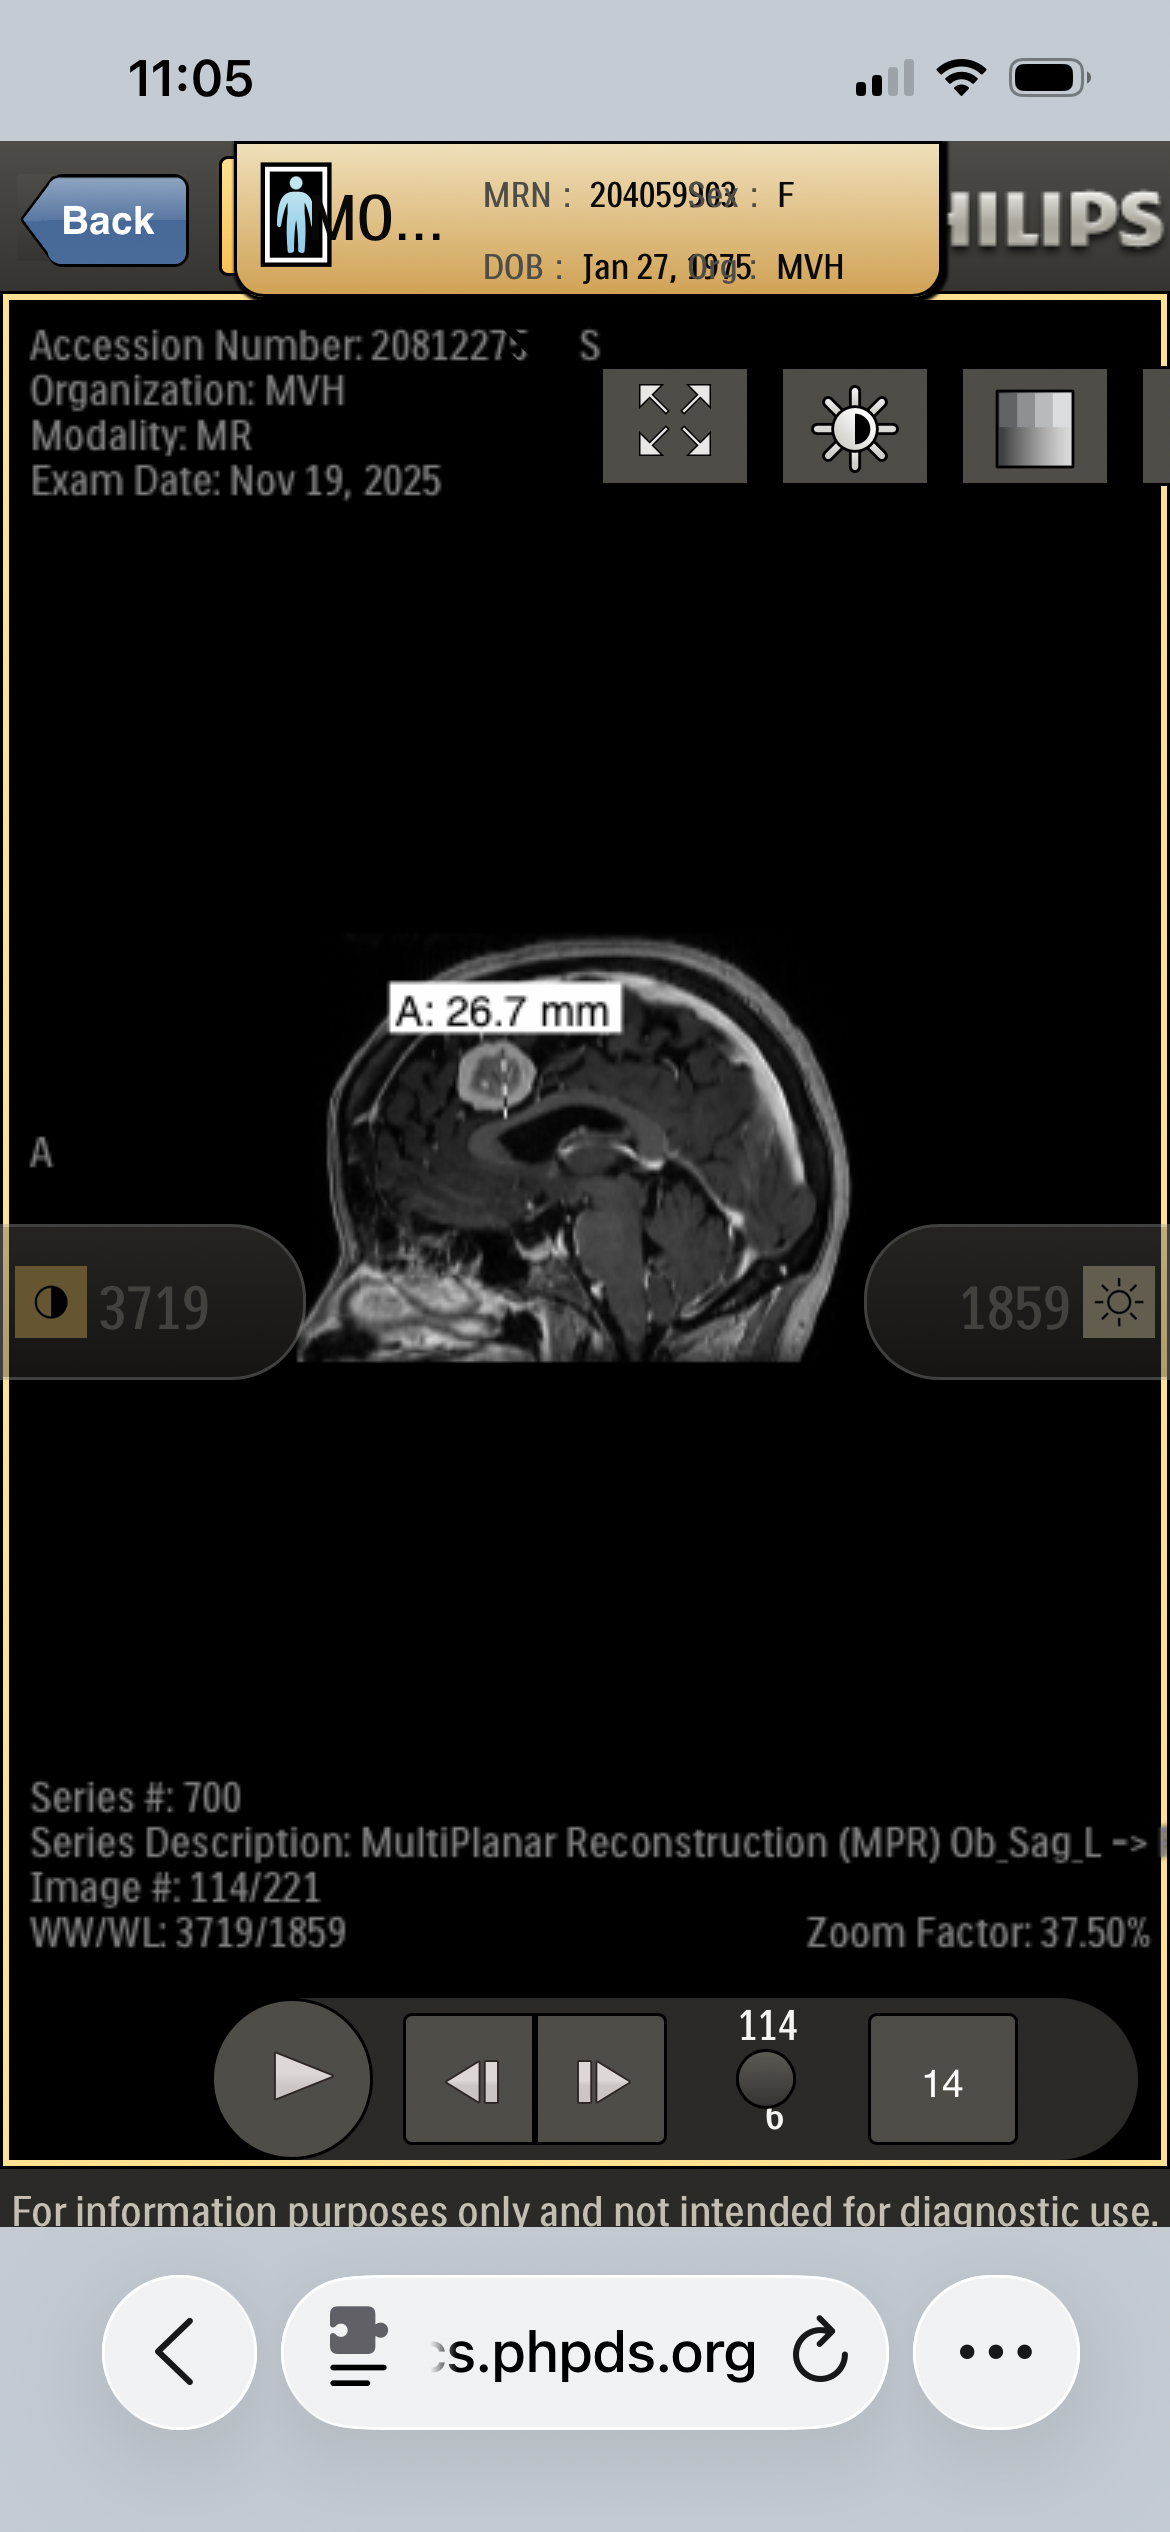

My name is Kory Burge and I'm raising funds for my mom, Angela Montgomery. She is a pediatric cancer survivor, prior pediatric oncology nurse and amazing mom and Mimi. When she was being treated for Stage III B Hodgkin’s Lymphoma in 1991 at the age of 16, they told my grandparents that the long-term concern is developing another cancer due to the harsh chemotherapy and radiation protocol, as well as heart and lung disease. As a parent, what choice do you have? Thirty-five years later, on November 18, 2025 after complaining for over three years to her doctors that something was desperately wrong and being denied an MRI, she convinced the ER doctor to do a CT on her head. They found two large brain tumors, one of which is pressing on and displacing her brain stem. She also has some on her spine, but they’re not sure how many yet. MRI of her entire spine is coming March 6th. This has kept her from working and she has used her retirement down to the penny, and now cannot work, nor support herself through this. Please donate if you can and share this with everyone you know.

The plan is to have the first surgery on March 10th to remove the brain tumor currently displacing her brainstem before it starts causing seizures. It will be 10-12 hours long, then 3 days in ICU and 3 days on the unit. The next will be to remove the one in her frontal lobe.